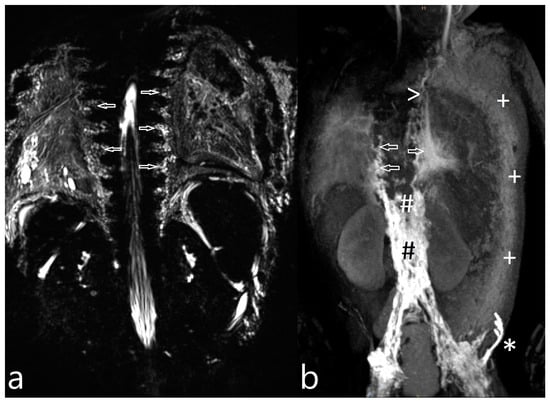

| 21 | 4 | increased signal mediastinum, hilum, lung le > ri | retrograde flow from TD with diffuse mediastinal and peribronchial perfusion | thoracic vertebrae 4–10 to left mediastinum | MCT diet, macitentan, alteplase inhalation, salbutamol, diuretics | glue embolization of TD | cast free after intervention (FU 1 a 4 m) tapering off sildenafil |

| 22 | 4 | increased signal (mediastinum), hilum/lung ri | retrograde lymphatic flow to mediastinum and lung parenchyma ri | from hilum to ri lung | fat reduced diet, sildenafil, alteplase/ fluticasone inhalation | selective glue embolization of 2 branches of TD | cast free after intervention (FU 4 a), cessation of fat-reduced diet, |